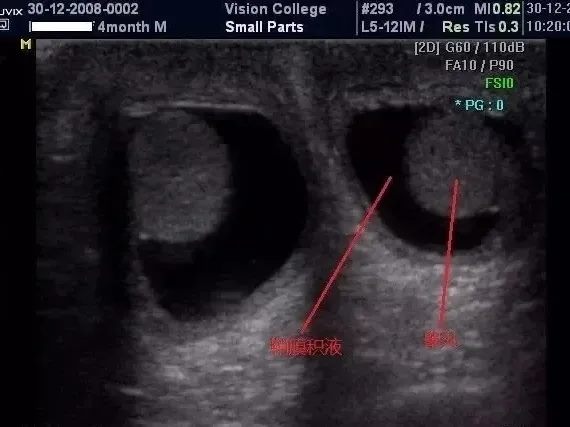

鞘膜积液是小儿最常见的鞘膜腹内壁的一种畸形。鞘膜积液是指鞘膜腔内积聚的液体超过正常量而形成的囊肿,本病可发生于任何年龄。当鞘膜本身或睾丸、附睾等发生病变时,液体的分泌增多与吸收减少失去平衡,形成鞘膜积液。

鞘膜积液的患者大多数多无自觉症状,有时肿块的大小可随体位的变动而变化,站立位时肿块增大,平卧位后阴囊肿块缩小或消失,则称之为交通性鞘膜积液,鞘膜积液的检查方法也很检查,彩超检查就可以明确诊断。